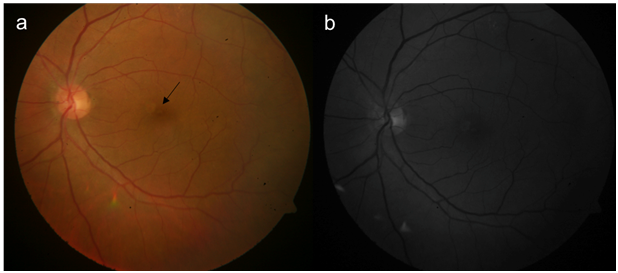

A 64-year-old female, presented with decreased vision in left eye, since 3 months. The visual acuity on Snellens chart was 20/30, N6 in right eye and 20/200 and N36 in left eye. Anterior segment examination showed both eyes with nuclear sclerosis of grade 3. The fundus of right eye was within normal limits with left eye optic disc and macula appeared normal (Figure1a &b). As vison was not correlating, optical coherence tomography (OCT) was done which revealed full thickness macular hole (FTMH) (Figure 2a). The dimensions of MH were, diameter of 286microns (m) and the basal dimeter of 486m. The patient was advised combined surgery but opted for only cataract extraction (phacoemulsification with a 2.8mm corneal incision) with single piece foldable intraocular lens implantation with no intraoperative complications. At 1 month follow up vision was 20/60, N24. OCT in left eye showed a separated vitreous with operculum with inner retinal layer apposition with outer lamellar hole (Figure 2b). At 2nd month, the inner retinal apposition increased, with decrease in outer lamella hole dimension (Figure 2c) and at 3rd month there was complete apposition of inner and outer retinal layers with final visual acuity of 20/40, N8 in left eye.

Figure 1 (a) Color fundus photograph of the left eye, black arrow points to greyish reflex of the separated posterior vitreous above the fovea. (b) red free photograph of the left eye.